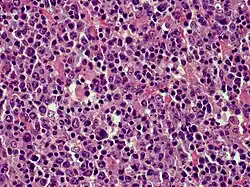

| Cutaneous diffuse large B-cell lymphoma | |

Cutaneous B-cell lymphomas (CBCL), more recently termed Primary cutaneous B-cell lymphomas and lymphoproliferative disorders (PCBCLPD), are a group of disorders that typically present as skin lesions consisting of proliferating B-cells. B-cells are a type of lymphocyte involved in regulating immune responses. (The "primary" used to designate cutaneous lymphomas indicates that the lymphoma was first diagnosed as limited to the skin and there was no evidence of spread to extracutaneous tissues for 6 months after the diagnosis was first made.[1]) Since its original definition in 1997, CBCL has been considered to have a varying number of subtypes by the European Organisation for Research and Treatment of Cancer, i.e., EORTC, and World Health Organization, i.e., WHO.[2] The latest revised classification of CBCL, which was published by EORTC in 2022, lists the following three main subtypes of CBCL (now termed PCBCLPD):[3]

- Primary cutaneous diffuse large B-cell lymphoma, leg type

Because recent studies had shown that primary cutaneous marginal zone lymphoma, which was formerly classified as a subtype of the MALT lymphomas: a) has a distinct microscopic histology and gene expression profile; b) spreads to extracutaneous tissue in only 4 to 8.5% of cases; c) has a 5 year disease-specific survival in excess of 99% even in patients not receiving aggressive therapy; and d) has pathological findings that overlap the benign cutaneous disorders termed cutaneous lymphoid hyperplasia. Consequently, EORTC, 2022, renamed primary cutaneous marginal zone lymphoma as primary cutaneous marginal zone lymphoproliferative disorder.[3] Primary cutaneous follicle center lymphoma is also an indolent lymphoma.[4] The majority of patients achieve complete remissions following surgery and/or radiation therapy. Its spread to extracutaneous tissues is rare (10%) and has a 5-year overall survival and disease-specific survival of 87% and 95%, respectively.[3] Primary cutaneous diffuse large B-cell lymphoma, leg type is an aggressive B-cell lymphoma that is often resistant to therapy and carries a poor prognosis,[5] i.e., they have a 5-year disease-specific survival rate of 43% or 70% depending on whether their cancer cells have or do not have, respectively, inactivating mutations in both of their CDKN2A genes.[6]